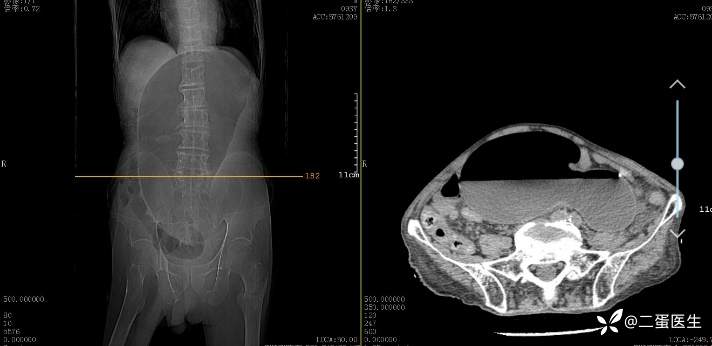

辅助检查: 影像学检查见巨大胃泡影,提示胃扭转伴胃扩张。

胃扭转也可以根据其异常旋转的轴的不同而分为器官轴(长轴)型(organoaxial volvulus)和系膜轴(短轴)型(mesenteroaxial volvulus)。器官轴型胃扭转是指胃以贲门与幽门部连线为轴发生的旋转,胃窦向前上方,胃底向后下方旋转,其结果是胃大弯以倒置位而位于胃小弯的上方,如上文中图1所示。器官轴型胃扭转是临床中最常见的胃异常旋转类型,约占胃扭转病例的60%,胃绞窄性坏死更常见于这种类型的胃扭转,发生率超过30%。系膜轴型胃扭转是指胃以连接胃大弯和胃小弯的垂直线为轴发生的旋转,胃窦移位到贲门部上方。系膜轴型胃扭转程度上通常<180°,且旋转通常与继发性解剖缺陷无关。